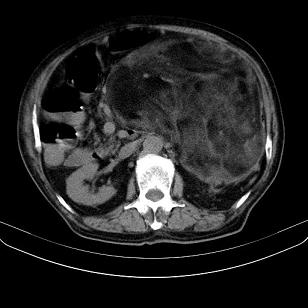

标题: CT21671:男,88岁,左上腹包块 [打印本页]

标题: CT21671:男,88岁,左上腹包块

患者因咳嗽而住院,自觉右上腹包块,无其他不适。

腹膜后高分化脂肪肉瘤

腹膜后脂肪肉瘤

腹膜生占位性病变,脂肪肉瘤可能。

左侧腹膜后脂肪肉瘤。